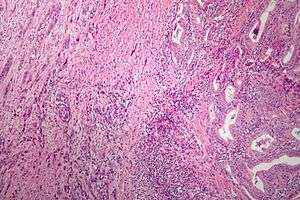

Micrograph of anaplastic thyroid carcinoma. H&E stain. | |

Anaplastic thyroid cancer (ATC) is a form of thyroid cancer which has a very poor prognosis due to its aggressive behavior and resistance to cancer treatments.[1] Its anaplastic cells have poor differentiation, including dedifferentiation.

Anaplastic tumors have a high mitotic rate and lymphovascular invasion.[2] They rapidly invade surrounding tissues (such as the trachea). The presence of regional lymphadenopathy in older patients in whom needle aspiration biopsy reveals characteristic vesicular appearance of the nuclei would support a diagnosis of anaplastic carcinoma.